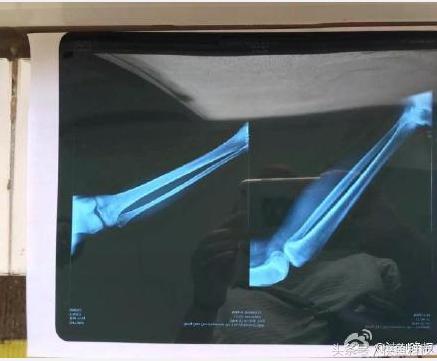

下圖是醫(yī)院診斷書(shū),后來(lái)青島市西海岸國(guó)際旅游度假區(qū)管理委員會(huì)在其官方微博@青島鳳凰島 通報(bào)稱(chēng),目前,金沙灘景區(qū)已啟動(dòng)應(yīng)急資金,退還該游客1200元,并對(duì)該糾紛的具體情況和處置過(guò)程將進(jìn)行調(diào)查處理。金沙灘景區(qū)對(duì)游客遇到的不愉快景區(qū)深表歉意,下一步將加強(qiáng)管理,營(yíng)造良好的旅游環(huán)境。